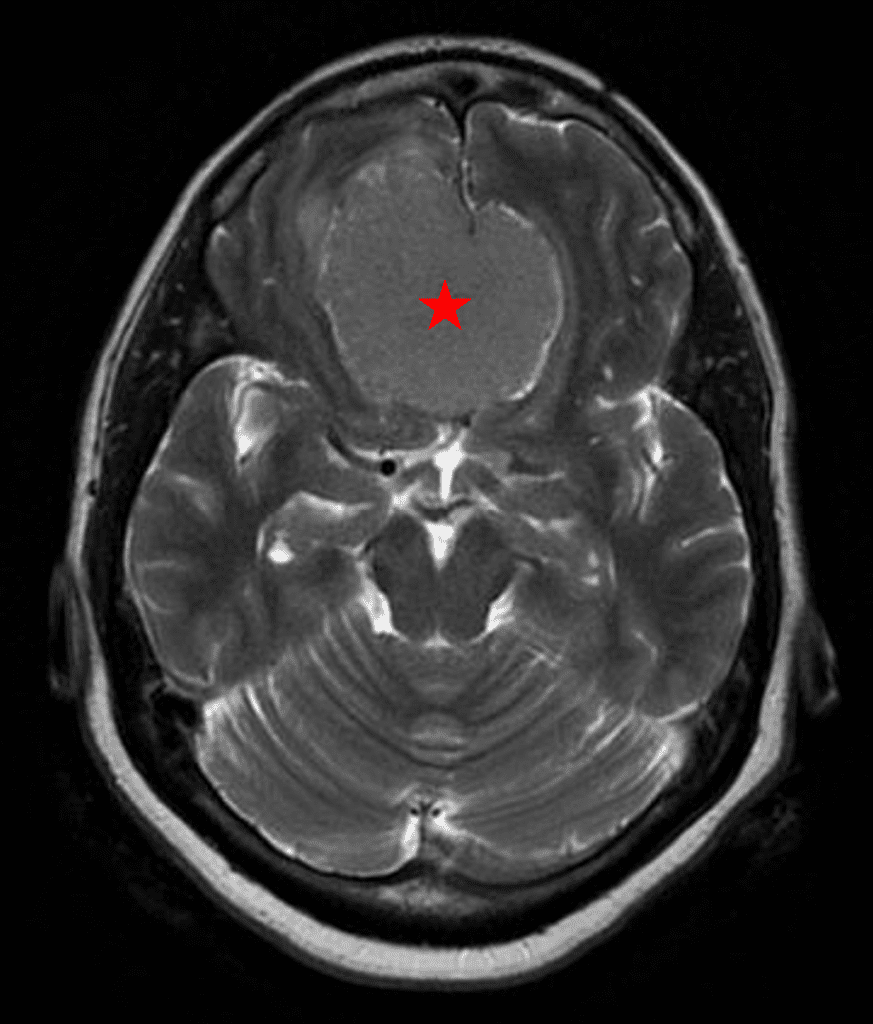

She was started on high-dose steroid and antiseizure prophylactic medicine. Surgical intervention was offered for mass effect, symptomatic relief, neurologic preservation, and histopathologic diagnosis. Dr. Gaudin performed a bifrontal craniotomy with complete resection of neoplasm through an interhemispheric and subfrontal approach. Postoperative imaging demonstrated a gross total resection without residual tumor and resolution of mass effect (Figure 1b and 2b). Intraoperative pathology was consistent with meningioma, WHO grade 1. She recovered very well, and was discharged home on postoperative day 3. On her follow-up outpatient visit, her preoperative symptoms had fully resolved, and her olfactory sense was maintained.

Figure 2b – Postoperative MRI demonstrating resolution of mass effect.